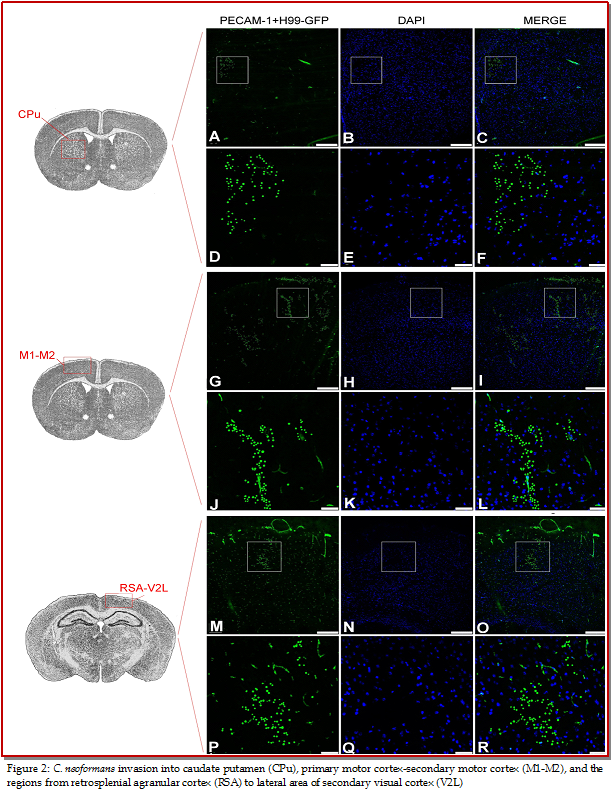

Aim of this study was to locate the brain regions where Cryptococcus interact with brain cells and invade into brain. After 7 days of intratracheal inocula-tion of GFP-tagged Cryptococcus neoformans strains H99, serial cryosections (10 ?m) from 3 C57 BL/6 J mice brains were imaged with immunofluorescence microscopy. GFP-tagged H99 were found in some brain regions such as primary motor cortex-secondary motor cortex, caudate putamen, stratum lucidum of hippocampus, field CA1 of hippocampus, dorsal lateral geniculate nucleus, lateral posterior thalamic nucleus, laterorostral part, lateral posterior thalamic nucleus, mediorostral part, retrosplenial agranular cortex, lateral area of secondary visual cortex, and lacunosum molecular layer of the hippocampus. The results will be very useful for further exploring the mechanism of C. neoformans infection of brain.